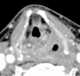

Intracranial tumor with erosion

Pott's puffy tumor, first described by Sir Percivall Pott in 1760, is a rare clinical entity characterized by subperiosteal abscess associated with osteomyelitis. It is characterized by an osteomyelitis of the frontal bone, either direct or through haematogenic spread. [Source: Wikipedia ]